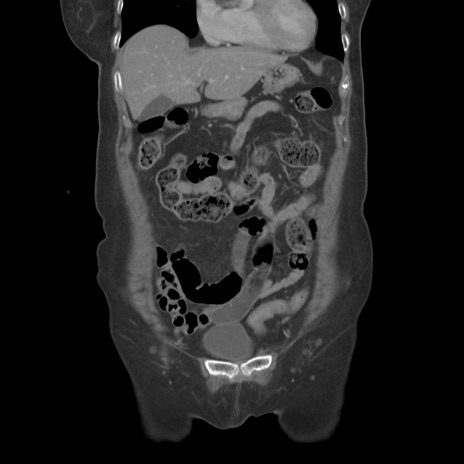

症例19(冠状断像)

【症例】80歳代女性

【主訴】下腹部痛

【現病歴】約8時間前より下腹部痛の出現あり、救急外来受診。

【既往歴】両側付属器切除

【身体所見】意識清明、下腹部正中に手術痕あり、その部位に一致して圧痛と反跳痛あり。腸蠕動音は亢進。

【データ】WBC 9300、CRP 0.15